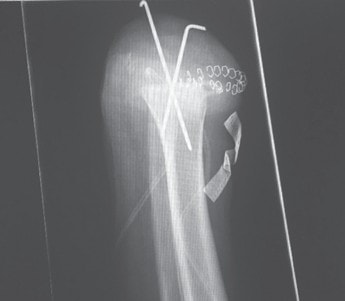

Ziel dieses Beitrages ist die Empfehlung eines Paradigmenwechsels in der postoperativen Behandlung auf der Grundlage jahrzehntelanger operativer und rehabilitativer Erfahrung in den ersten drei bis sechs Monaten nach der Amputation – wobei zu bedenken gilt, dass es eigentlich kein „echter“ Paradigmenwechsel ist, da die unten dargelegten Empfehlungen früher bereits praktiziert wurden und sich bewährt haben (Abb. 1 u. 2).